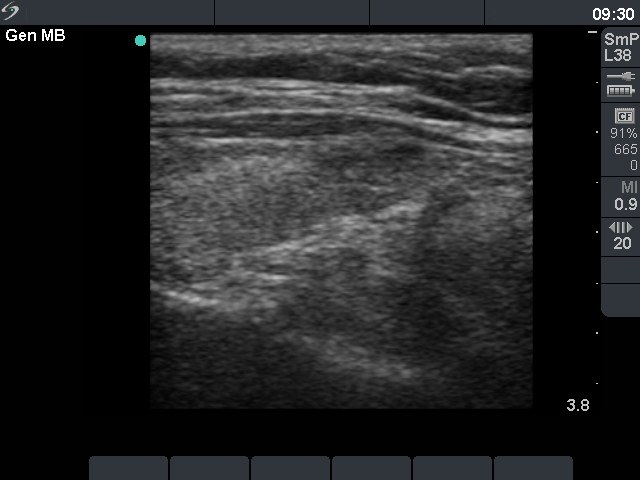

Chronic lymphocytic thyroiditis - Case 79. (ultrasonographic picture 2)

Right lobe, longitudinal scan.